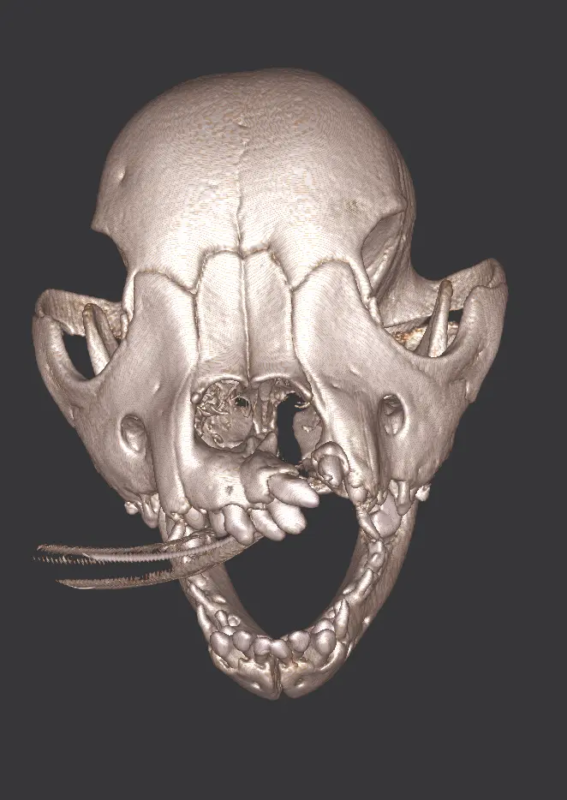

The Center now provides advanced imaging via cone beam CT. Cone beam CT is excellent for visualization of bony structures of the skull, nasal cavity, teeth, and ears. Cone beam CT is especially helpful for diagnosing dental disease and evaluation of jaw fractures. It can also be useful for evaluating the sinuses and tympanic bulla. Cone beam CT can be used in conjunction with nasal biopsy and culture to evaluate nasal discharge whether chronic or acute.

Pets can be involved in trauma that can cause fractures to their head, teeth, and jaw bones. Correctly repairing these fractures is extremely important for your pet to have normal function of their mouth. If a jaw fracture is allowed to heal in an abnormal position, your pet may have great difficulty chewing and can be in significant pain. Many fractures can be successfully treated with minimally invasive oral procedures, but more complicated cases may require bone plating techniques. The Center offers cone beam CT imaging which provides extremely detailed images of the bones of the head and skull. Advanced imaging with CBCT facilitates selection of the best surgical technique to get your pet back to eating and comfort as soon as possible.